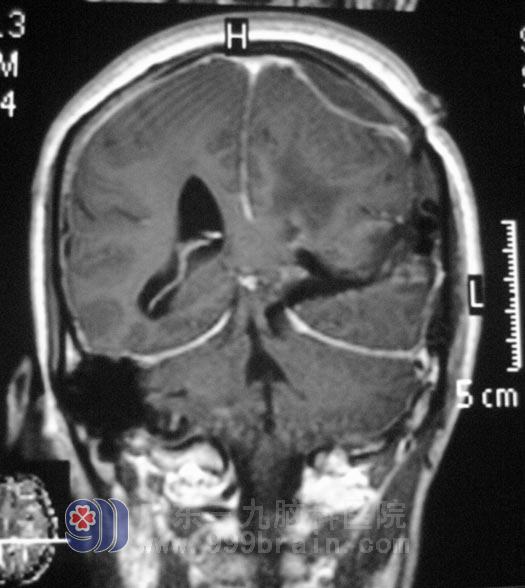

手术过程顺利,吴女士经过住院治疗后,头痛、双下肢不自主抖动症状已经消失,近期准备出院。术后病理回报为:(左侧脑室)纤维型脑膜瘤,WHO I 级。http://www.999brain.com/